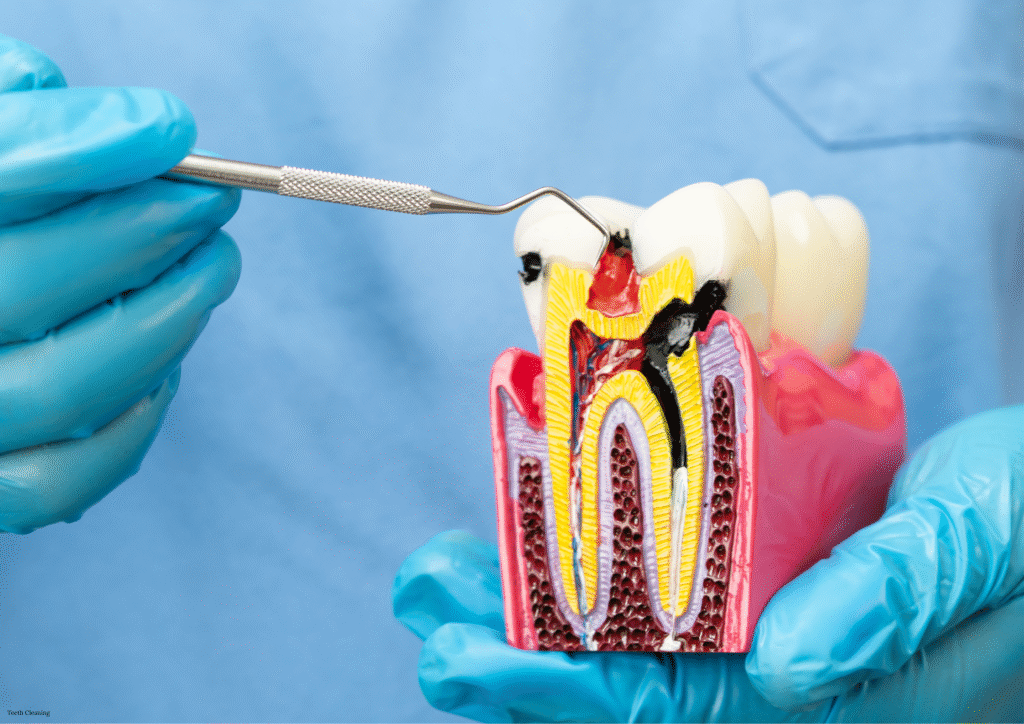

RCTs Done

0

+